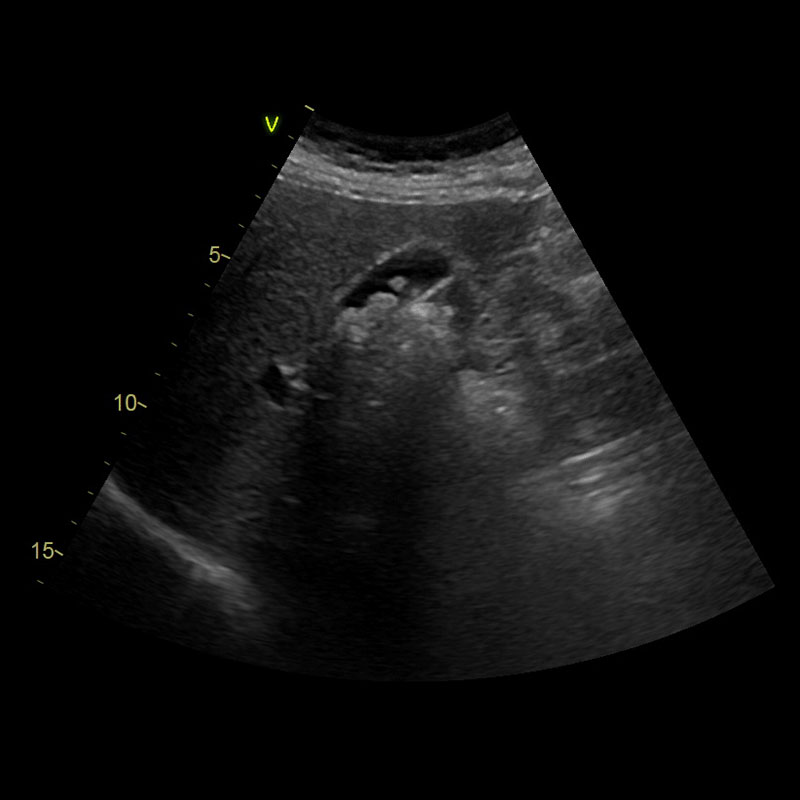

Im Oberbauchultraschall untersuchen wir die Organe Leber, Gallenblase mit Gallengängen (Abb.), Bauchspeicheldrüse, Nieren sowie die Aorta. Die Untersuchung führen wir bei Bauchbeschwerden oder auffälligen Laborwerten durch (z.B. erhöhten Leberwerten).

Ultraschall ist die optimale Untersuchung für die Beurteilung der sogenannten parenchymatösen (geweblichen) und der flüssigkeitsgefüllten Bauchorgane. Daher können wir die Bauchspeicheldrüse, Leber und Nieren beurteilen sowie die Blutgefäße und das Gallengangssystem inkl. der Gallenblase. Im Ultraschall diagnostizierbare Erkrankungen sind z.B. die Fettleber, Gallen- oder Nierensteine oder auch das Aortenaneurysma. Auch in der Früherkennung von Tumoren der Leber und Nieren spielt der Ultraschall eine große Rolle, ebenso wie in der Nachsorge bei zahlreichen Krebserkrankungen zum Ausschluss von Lebermetastasen.